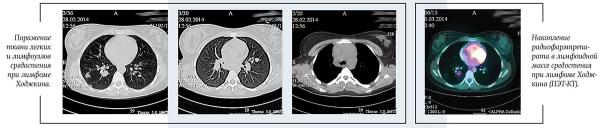

В настоящее время стандартом обследования при ЛХ является позитронно-эмиссионная томография с 18F-флюородезокси-глюкозой, совмещенная с КТ (ПЭТ-КТ).

ПЭТ-КТ позволяет точнее определить вовлеченные в опухолевый процесс лимфатические узлы и области организма, определить стадию и объем лечения. В нашей стране данный метод стал доступен для всех пациентов с ЛХ с 2017 года.

С активным внедрением ПЭТ-КТ в диагностику лимфом началась новая эра в лечении детей с ЛХ. ПЭТ-КТ стала активно применяться не только для стадирования, но и для оценки статуса ремиссии и раннего ответа на терапию. Быстрое достижение ПЭТ-негативности является маркером чувствительности опухоли к химиотерапии. Появился способ выявлять пациентов, для которых возможно отказаться от ЛТ. С 2017 года ЛТ отменяют пациентам с ранними стадиями, достигшим полной ремиссии по данным ПЭТ-КТ после завершения этапа ПХТ.

ПЭТ-КТ: в переднем средостении верхнего этажа срединно с акцентом вправо опухолевая масса; 36ґ73ґ60 мм. Изолированно лежащие увеличенные лимфоузлы: паратрахеальные и бифуркационные, до 15 мм; парастернально справа, до 18 мм. По данным ПЭТ: накопление РФП помимо вышеописанных узлов — в правом корне (бронхопульмональные л/узлы), в л/узлах — прекардиально справа, в кардиодиафрагмальной области слева, параэзофагеально (на КТ узел, 14 мм).

Очагов патологической плотности в легочной паренхиме не выявлено. Легочной рисунок не изменен. Долевые и сегментарные бронхи проходимы. Корни легких не расширены, структурны. Подмышечные л/узлы не увеличены. Плевральные полости свободны. Мягкие и костные ткани грудной клетки без структурных изменений. Отмечается увеличение забрюшинных л/узлов, до 23 мм; общих подвздошных до 15 мм. На ПЭТ патологическое накопление РФП помимо вышеописанных узлов — в воротах печени, в наружных подвздошных л/узлах, в селезенке.

В левой подвздошной кости определяется очаг гиперденсивной плотности с мелкобугристыми контурами, размером 10,5ґ6,6 мм. На ПЭТ также отмечается повышенное накопление РФП в телах позвонков С6, Тн4, L5, S1; ребрах; костях таза.

Заключение: лимфопролиферативное заболевание с поражением лимфоузлов по обе стороны диафрагмы, селезенки, костей.

Получен полный метаболический ответ по данным ПЭТ-КТ после этапа ПХТ. С целью консолидации ремиссии проведена лучевая терапия на зоны инициального поражения в СОД=20 Гр.